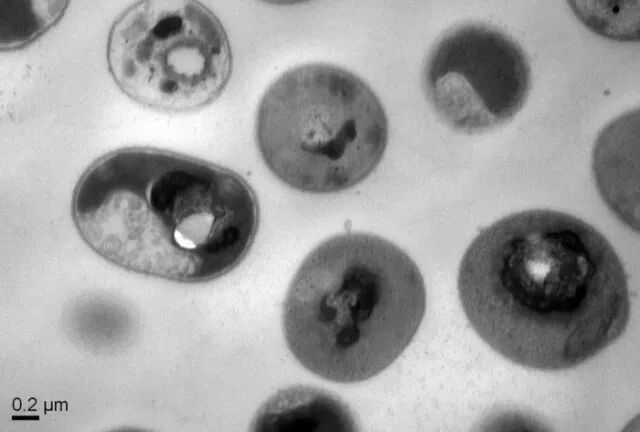

合成分子被称为胍官能化聚碳酸酯,被发现既可生物降解又对人体细胞无毒。实质上,带正电的合成聚合物进入活体并通过导入微生物膜的相关负电荷而特异性结合某些细菌细胞。一旦与细菌连接,聚合物穿过细胞膜并触发细胞中蛋白质和DNA的固化,杀死细菌。